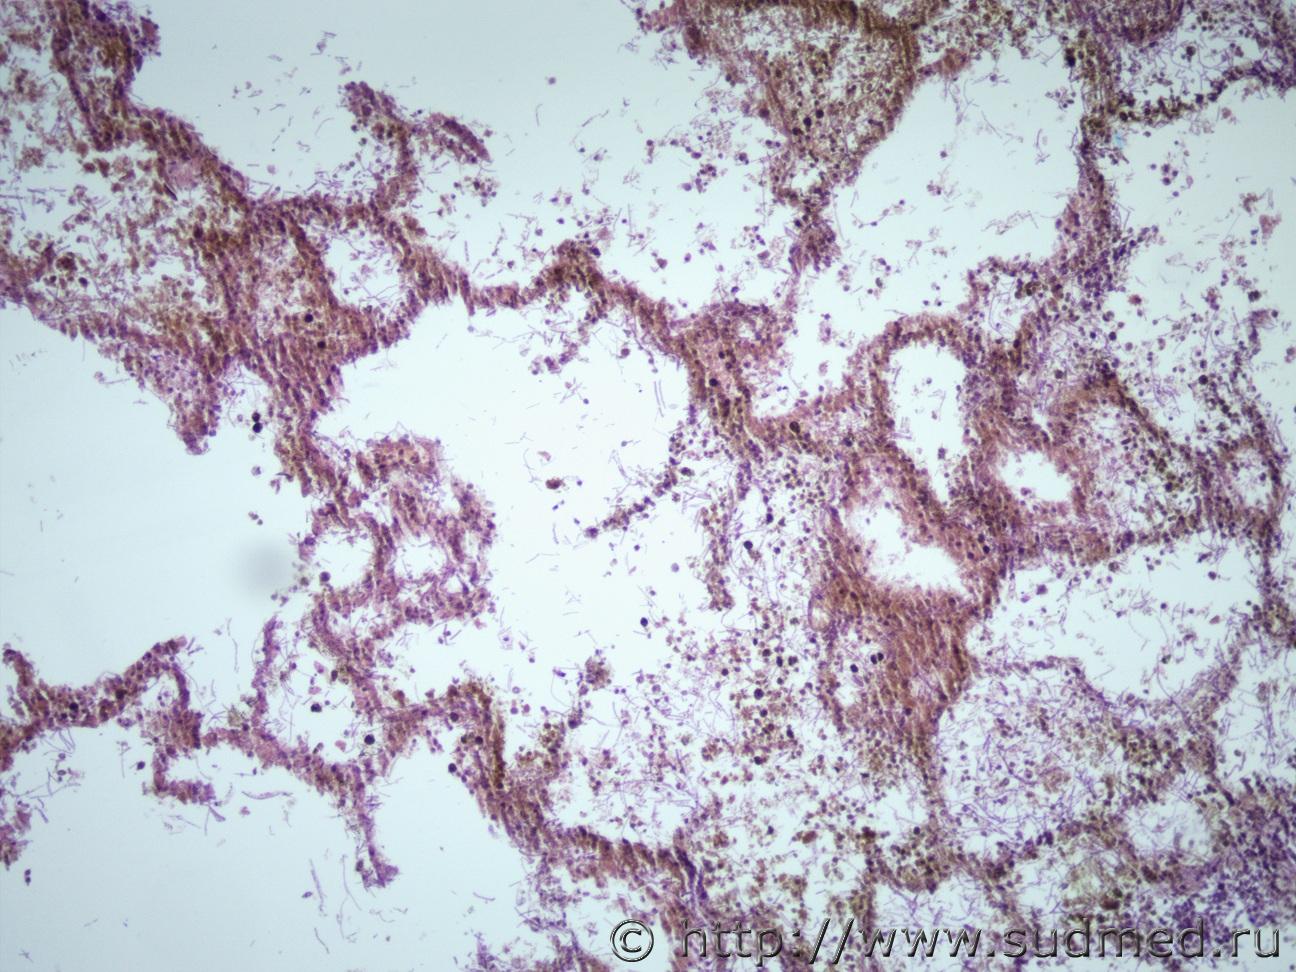

Добрый день уважаемые коллеги. Возник вопрос, точнее хочется уточнить для себя. В первые сталкиваюсь с такой пневмонией, с картинок атласов очень похоже на аспергиллез, но хочется окончательно убедится. Судебная медицина - Прикрепленное изображение Судебная медицина - Прикрепленное изображениеСудебная медицина - Прикрепленное изображениеСудебная медицина - Прикрепленное изображениеСудебная медицина - Прикрепленное изображение

По всему - грибы. ВИЧ? Сколько лет?

похоже на аспергиллез

На одних фото - гнойный аспергиллёз,на других - аспергиллёз-мицетома.

Верно! Аспергиллезная пневмония.